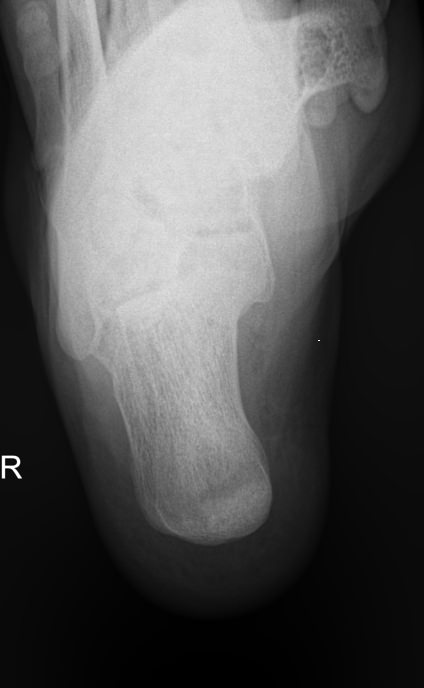

Назад Рентген пяточных костей в боковой проекции

Пяточная кость ― самая крупная среди костей стопы. Нагрузка, приходящаяся на нее, колоссальна. Отсюда и частая травматизация, связанная как со спортом, так и с бытовой и профессиональной деятельностью. Также все патологии, которые развиваются в костной ткани, могут появиться и в пяточной кости. Рентген ― наиболее часто назначаемый вид диагностики при поражении пятки.

На рентгенограмме будут отчетливо видны все структурные изменения, произошедшие с самой пяточной костью и тканями вокруг нее.

Что покажет рентген пяточных костей в боковой проекции

• Целостность кости: переломы, отломки, смещение;

• Состояние костной ткани: разрежение, склерозирование, некроз и другие изменения;

• Конгруэнтность суставных поверхностей и состояние щелей, попавших в область снимка: нормальные, измененные;

• Отечность и инородные тела в мягких тканях пятки;

• Новообразования: опухоли, остеофиты.

Стоит отметить, что остеофиты не являются причиной плантарного фасциита, а вырастают в ответ на хроническое раздражение мягких тканей и свидетельствуют о глубокой стадии заболевания.